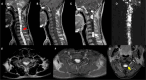

Hemangioblastomas are rare, benign, and highly vascular tumors of the central nervous system, often associated with von Hippel-Lindau (VHL) syndrome, an autosomal dominant disorder characterized by multiple tumors. We present a case of a 32-year-old male with progressive headaches, visual disturbances, and motor deficits, who was diagnosed with multiple hemangioblastomas in the cervical-thoracic spinal cord and bilateral cerebellum through MRI. Surgical resection and histopathological biopsy confirmed the diagnosis. This case highlights the critical role of MRI in diagnosing and managing VHL-associated hemangioblastomas and underscores the importance of regular imaging for early detection and intervention of new or recurring tumors, optimizing patient outcomes.